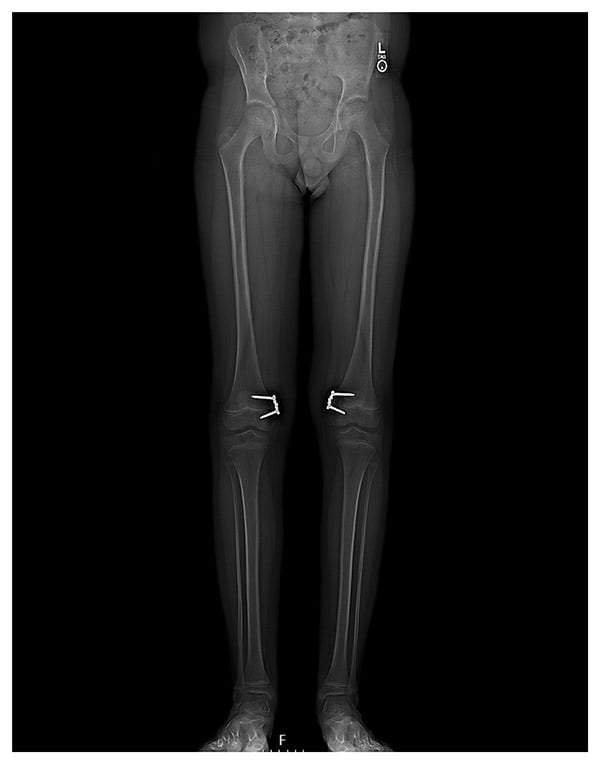

Nine months postoperatively, X-rays showed correction of the patient’s genu valgum (Figure 3). He was subsequently recommended for removal of hinge plates and for concurrent right-sided MPFL reconstruction with hamstring allograft and lateral retinacular release due to a symptomatic right knee (history of multiple patella dislocations/subluxation and persistent patellofemoral instability). The patient will be followed postoperatively and displays no complications in the left knee following the initial surgery.

Figure 3: 9 months postoperative EOS radiograph showing correction of genu valgum, before hardware removal.